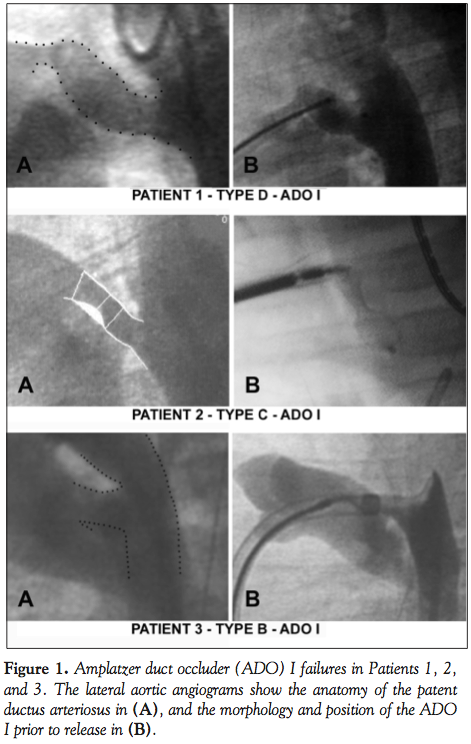

For the ADO I, immediate closure was achieved in 40% of the cases (30/74 patients), rising to 94.6% (70/74 patients) at 24 hours, and to 96% (71/74 patients) at 6 months. Thus, the ADO I failed to close the PDA in 3 patients. The first patient (Patient 1 in Table 2 and Figure 1) was a 3-year-old, 17 kg boy with a 4 mm type D PDA which was initially closed with an 8-6 ADO I. The Amplatzer asymptomatically migrated to the abdominal aorta before discharge from the hospital. The shunt seen on the follow-up serial echocardiograms was thought to

be a residual shunt, and the migration was diagnosed only 1 year later. We believe that this migration occurred on the second day, because the predischarge chest x-ray examined retrospectively 1 year later did not show the radio-opaque markers of the ADO in the usual position. The device was embedded asymptomatically in the abdominal aorta, facing the celiac artery (Figure 3A, black arrow). Attempts at its percutaneous removal 1 year later failed due to strong adhesions to the aortic wall; hence, it was left in place since it wasn’t obstructive. This failure was considered recovered, as the PDA was percutaneously closed using a 14-12 ADO I (Figure 3B); the device was oversized to achieve incomplete deployment of the aortic disc inside the PDA (Figure 4). The first ADO is still in the abdominal aorta with no gradient on the serial Doppler studies for 6 years now. The second patient (Patient 2 in Table 2 and Figure 1) was a 7-month-old who weighed 6.5 kg, with a 2.2-mm wide and 9-mm long type C PDA. When it was advanced and correctly positioned in the PDA, the 6-4 ADO I became severely kinked with a very narrow angle, and thus kept sliding backward and protruding into the pulmonary artery during every release attempt. The device wasn’t released, the procedure was abandoned, and the patient was referred for surgery 3 months later. This happened before the ADO II era. The third ADO I failure (Patient 3 in Table 2 and Figure 1) was a 6-month-old, 7 kg baby girl with a type B, 6.6 mm duct; the 10-8 ADO I totally obstructed the aortic flow and was retrieved before releasing. The patient was also referred for surgery.

Interestingly, all 3 recovered failures were attributed to migration of the device, and all 3 definite failures referred to surgery were due to the protrusion of the device, and obstruction of the aorta or pulmonary artery. Concerning migration, one may assume that if an ADO is completely deployed, secondary migration should be obviously due to the small size of the device relative to the diameter of the PDA; this assumption was confirmed in our series by the successful secondary occlusion of the ducts using larger devices in all 3 patients. The patient illustrating best the advantages of device oversizing was Patient 1. In this patient, the measured minimal diameter of the 20-mm long type D PDA was around 4 mm. An 8-6 ADO I was placed in the aortic restriction, which resulted in the migration of the device. This failure was recovered by modifying the deployment technique of the ADO I; the device was oversized on purpose (14-12 ADO I), to obtain an incomplete deployment of the aortic disc inside the duct. The excessive length of this PDA prevented protrusion of the device into the pulmonary artery after its release.3 This technique was successfully reiterated in other patients with type C ducts measuring more than 5 mm. However, care must be taken with device oversizing; generous oversizing may tear the duct wall. Oversizing needs also a small restriction area somewhere in the duct. In a 30 kg, 14-year-old patient with severe pulmonary hypertension and a short type A PDA, the ADO I was largely oversized, but normally deployed, so that the pulmonary narrowing transformed the pulmonary part of the device in a retention disc. This prevented aortic migration of the ADO that might have been facilitated by pulmonary hypertension. This technique is not applicable in small infants.